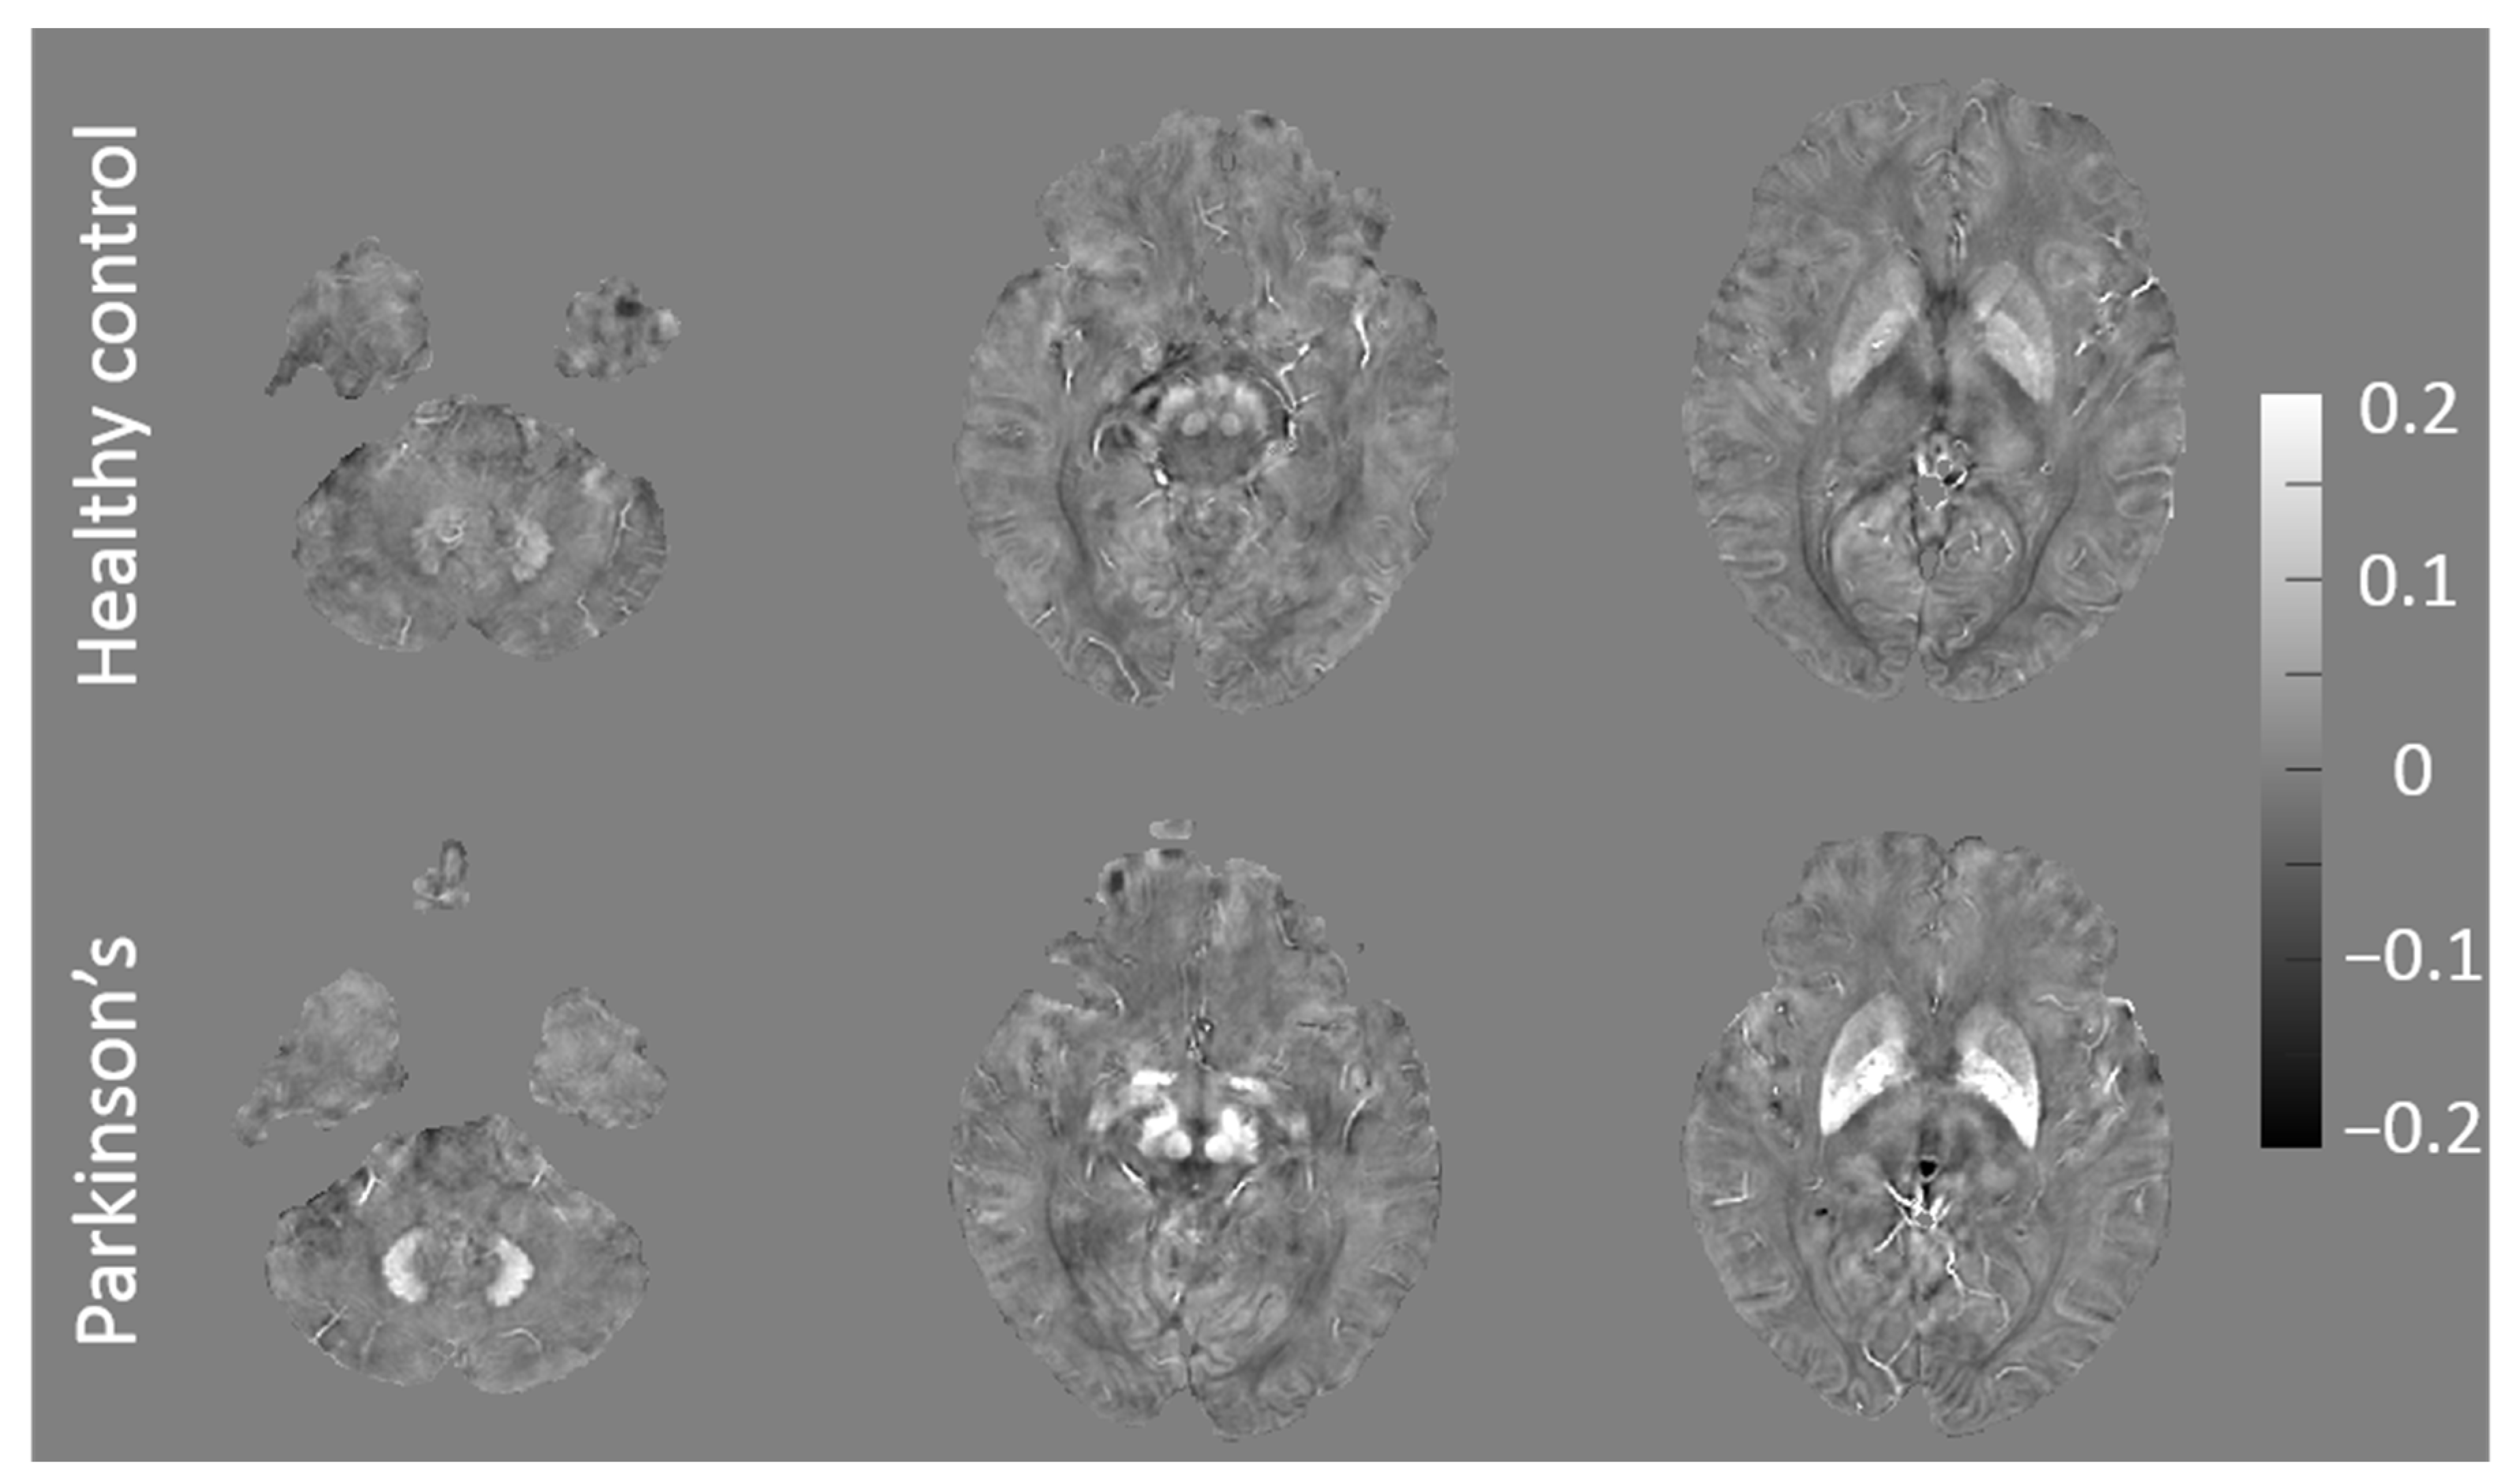

3.1. QSM and F-Scores for Patients with Early PD and HCs

| ROI c | Mean QSM k Value ± SD, ppm | F-score l | |

|---|---|---|---|

| Patients with Early PD (n = 24) | HCs (n = 27) | ||

| GP d | 0.142 ± 0.034 | 0.134 ± 0.038 | 14.634 |

| DN e | 0.101 ± 0.031 | 0.095 ± 0.026 | 11.461 |

| SNr f | 0.131 ± 0.044 | 0.115 ± 0.044 | 11.261 |

| SNc g | 0.130 ± 0.043 | 0.125 ± 0.041 | 9.349 |

| RN h | 0.102 ± 0.032 | 0.097 ± 0.034 | 9.251 |

| CN i | 0.070 ± 0.025 | 0.059 ± 0.021 | 7.497 |

| PUT j | 0.109 ± 0.049 | 0.094 ± 0.025 | 6.910 |